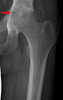

Juxta-articular chondroma